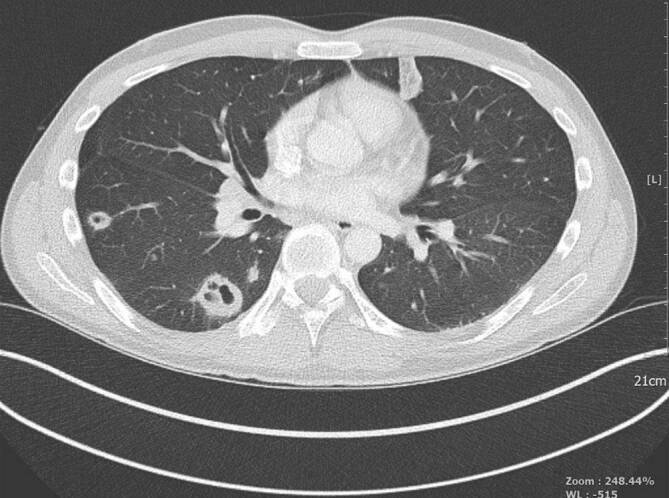

Febrile Neutropenie mit Lungeninfiltraten

Lungeninfiltrate können bei bis zu 25 % der Patienten mit schwerer und prolongierter Neutropenie nachgewiesen werden [10]. Zu den möglichen kausalen pathologischen Keimen gehören Aspergillus spp., Pneumocystis jirovecii, Mycoplasma pneumoniae, Chlamydia pneumoniae, Legionellen, Nocardia asteroides, multiresistente gramnegative Bakterien, Mykobakterien, respiratorische Viren sowie Fadenpilze.

Bei Patienten mit febriler Neutropenie und respiratorischen Symptomen ist die Mehrschicht- oder hochauflösende Computertomographie der Lunge das diagnostische Mittel der Wahl. Bei den meisten Patienten ist die Anwendung von Kontrastmittel nicht erforderlich. Alternativ kann die Durchführung einer Magnetresonanztomographie vorgenommen werden. Die Diagnostik soll innerhalb von 24 h nach Indikationsstellung stattfinden ([7, 10], Abb. 1).

Die Diagnostik soll innerhalb von 24 h nach Indikationsstellung stattfinden

Beim positiven Nachweis von Infiltraten soll eine bronchoalveoläre Lavage, aus dem das auffällige Areal versorgenden Segmentbronchus, erfolgen. Auch diese soll innerhalb von 24 h nach Indikationsstellung durchgeführt werden, sofern keine kritische Hypoxämie vorliegt. Die Aufarbeitung der bronchoalveolären Lavage umfasst die Polymerasekettenreaktion (PCR) für Mycobacterium tuberculosis, PCR und direkte Immunfluoreszenz für Pneumocystis jirovecii, Aspergillusantigen (Galactomannan-ELISA, „enzyme-linked immunosorbent assay“) sowie Bakterienkulturen inklusive Legionella spp. und Mykobakterien. Außerdem werden auch PCR für Zytomegalievirus (CMV), Respiratory-Syncytial-Virus, Influenza A/B, Parainfluenza 1–3, Metapneumovirus, Adenovirus sowie Varizella-Zoster-Virus empfohlen.

Eine antimykotische Therapie soll beim Nachweis von Infiltraten begonnen werden, die nicht typisch für eine Pneumocystispneumonie oder eine bakterielle Lobärpneumonie sind. Therapie der Wahl ist Voriconazol oder liposomales Amphotericin B [11]. Beim bildgebenden Verdacht auf Pneumocystispneumonie und einer neu aufgetretenen LDH-Erhöhung soll eine Therapie mit hochdosiertem Trimethoprim-Sulfamethoxazol auch vor der Durchführung einer bronchoalveolären Lavage erfolgen. Nach einer erfolgreichen Therapie sollen die Patienten eine orale Sekundärprophylaxe erhalten. Bei Patienten mit Nachweis von Pseudomonas aeruginosa sollte eine Therapie mit pseudomonaswirksamen β‑Laktamen wie Piperacillin/Tazobactam, Ceftazidim, Imipenem/Cilastatin, Meropenem oder Cefepim in Kombination mit einem Aminoglykosid verwendet werden. Bei Kontraindikationen gegen Aminoglykoside könnte stattdessen Ciprofloxacin zum Einsatz kommen [7, 10].

Wir danken dem Institut für diagnostische und interventionelle Radiologie (Prof. Dr. Günther Wittenberg) und dem Institut für diagnostische und interventionelle Neuroradiologie (Prof. Dr. Randolf Klingebiel) für die Überlassung der CT- bzw. MRT-Bilder.